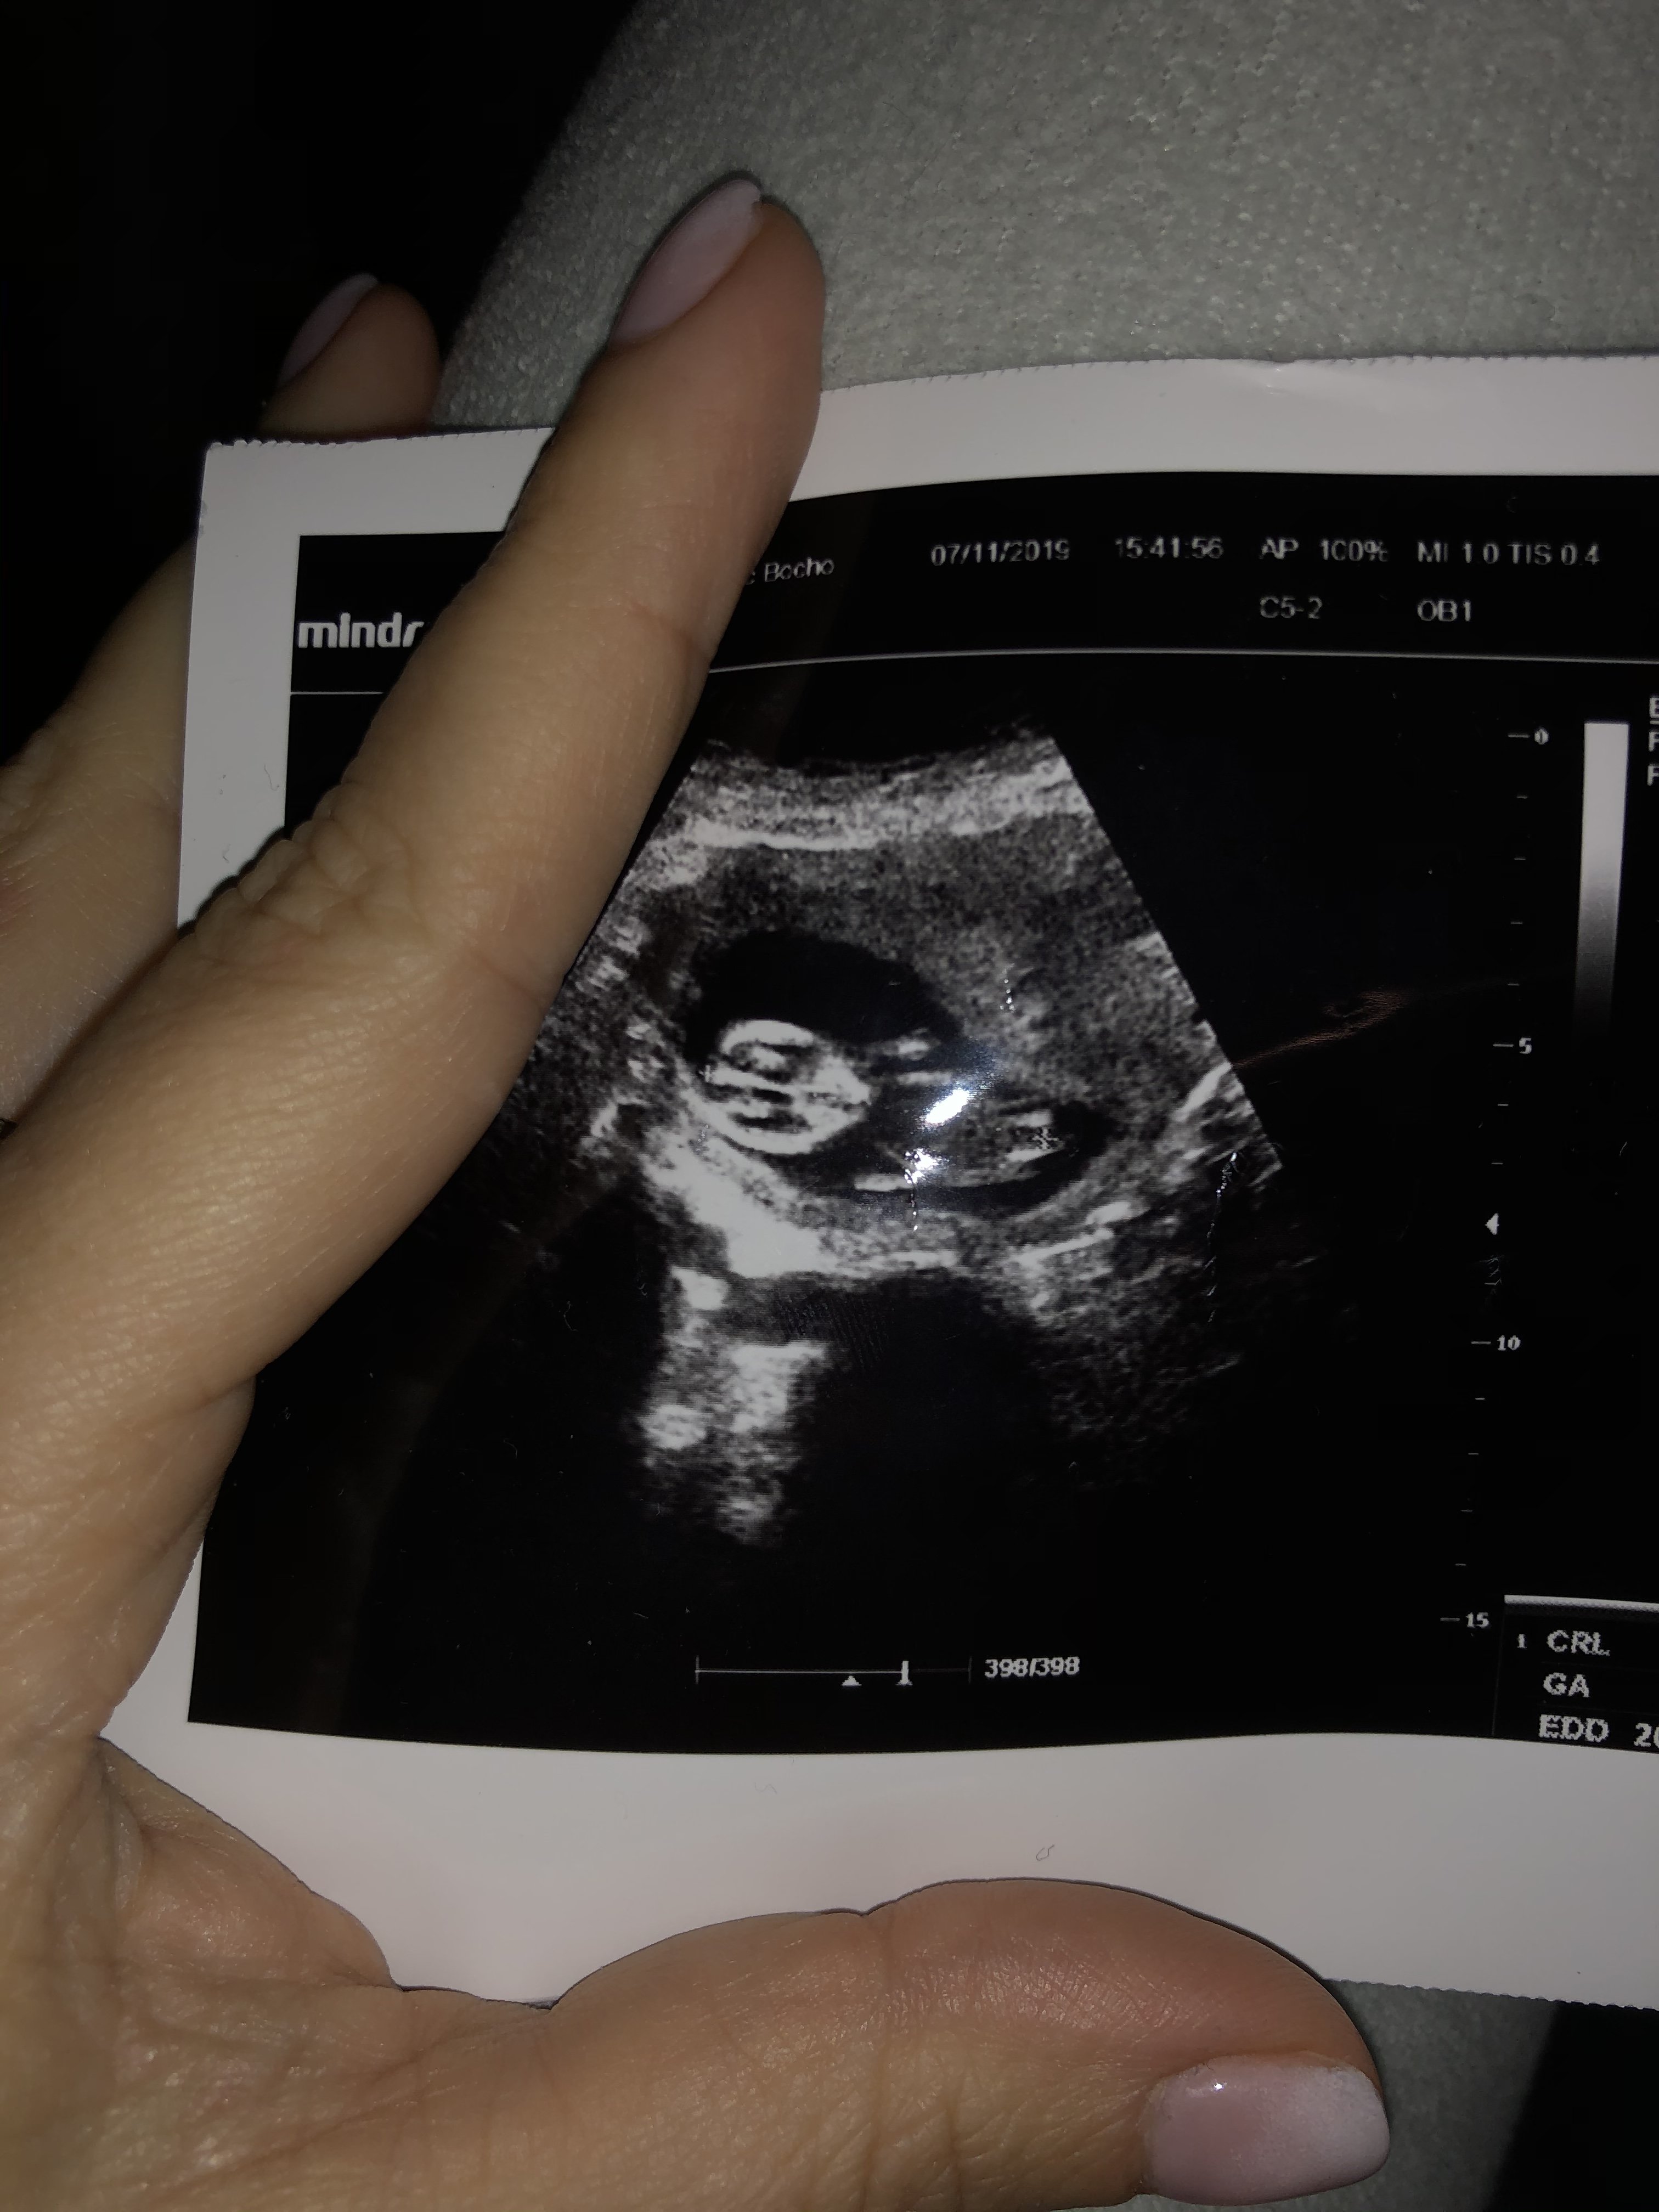

Usg chłopak czy dziewczynka

Witam w 19 tygodniu ciąży dowiedziałam się ze będę miała dziewczynkę w 20 tyg okazało się jednak , że to chłopak. Sama już nie wiem bo na jednym usg widać na pewno dziewuche a na drugim chłopca. Może to pempowina ?? Może ktoś mi pomoże rozwiązać ta zagadkę